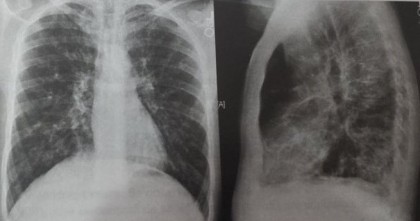

Atelectazia pe radiografia toracică

Toate formele de atelectazie au în comun o pierdere de volum ce interesează parțial sau total plămânul, determinând o densitate crescută a plămânului implicat. Plămânul normal este negru pe radiografia toracică deoarece conține aer. Atunci când aerul este substituit de ceva ce are densitate de lichid sau țesut moale sau dacă aerul este resorbit (cum se întâmplă în atelectazie), acea parte a plămânului devine mai albă (mai densă, mai opacă).

Aspectul radiologic constă într-o opacitate omogenă însoţită de micşorarea volumului pulmonar şi toracic. Opacitatea are caractere retractile, este atrasă traheea, mediastinul, cupola diafragmatică, peretele toracic, iar regiunea pulmonară respectivă este mai mică. La radioscopie, se observă în timpul inspiraţiei, pendularea mediastinului către atelectazie (semnul lui Holzknecht, Jakobson).

Semne de atelectazie pe radiografia toracică:

- deplasarea scizurilor pulmonare interlobare spre aria de atelectazie;

- creșterea densității plămânului afectat;

- deplasarea structurilor toracice mobile (trahee, cord, hemidiafragmul ipsilateral cu atelectazia);

- hiperinflația lobilor ipsilaterali neafectați sau a plămânului controlateral.